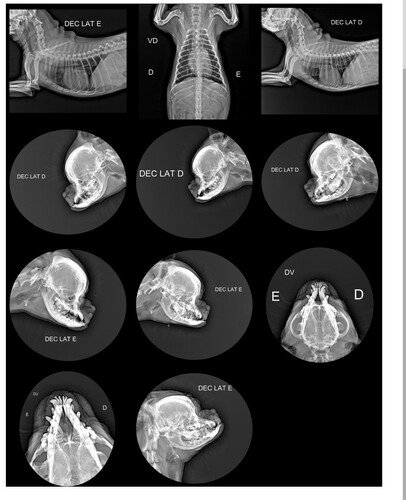

Amigos venho pedir ajuda nesta vaquinha para ajudar no tratamento do meu cachorrinho o nome dele é Frederico tem 7 anos está com uma neoplasia no nariz. Descobri tem pouco dias , elê ficou muito gripado , tomou remédio e os sitomas retorna logo aPós .apareceu neste intervalo um caroço no nariz, foi feito raio-x e no exame acusou a neoplasia nasal , ai comecei a fazer os exames e todos deu o tumor . Estou neste momento aguardado a última biopsia qué leva 21 dias chegar para comcecar o tratamento.Fiz todo os exames na clínica apaixonado por 4 patas em olaria . E o tratamento sera no espaço arp no oncologista . Então preciso de arrecada pelo menos a metade do valor ate chega o resultado .